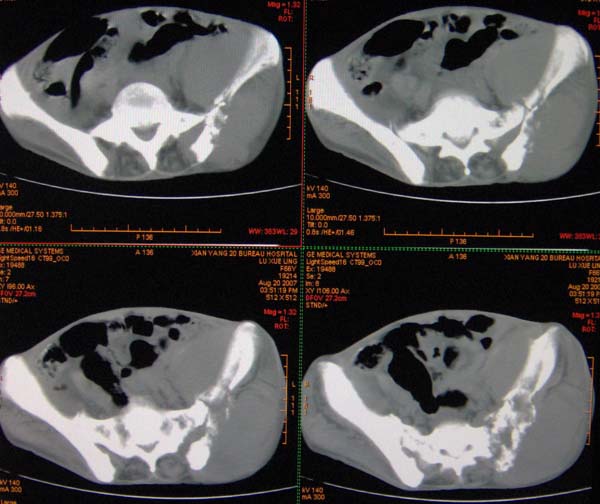

以下是引用ybing在2007-8-22 20:31:00的发言:[br]左侧髂骨溶骨样破坏;软组织肿块形成;其内未见肿瘤骨考虑纤维肉瘤或滑膜肉瘤不除外转移瘤

以下是引用qiushi在2007-8-22 21:39:00的发言:[br]双侧髂骨、骶骨侧快呈溶骨样骨质破坏,边缘模糊,左侧髂骨见骨折线,左侧髂部见软组织块影。考虑骨纤维肉瘤(中央型)伴病理性骨折,不排除骨髓瘤。建议本--周氏蛋白检查。[br] 鉴别点:[br] 骨纤维肉瘤,中央型者示边缘模糊的囊状溶骨破坏,一般无骨膜反映,可膨胀变形,突破骨皮质可形成软组织肿块,或并发病理性骨折。[br] 骨髓瘤,常表现为广泛的骨质疏松,皮质变薄或破坏,呈粟栗状、穿凿状、鼠咬状骨质破坏,边缘清晰,周围无硬化。[br] 骨转移瘤(溶骨型),表现为虫噬样、泡沫状圆形或卵圆形破坏区,很少出现软组织块影。[br][br][本贴已被 qiushi 于 2007-8-23 6:20:19 修改过]